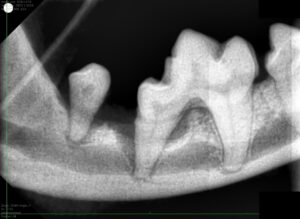

11歳トイプードルの歯科処置

こんにちは! 世田谷区等々力のけいこくの森動物病院です。 今回は歯周病治療を行ったトイプードルさんのご紹介です。 症例 今回は11歳のトイプードルさん。 歯磨きを毎日行ってい

5歳のノーフォークテリアさんの歯周病治療

こんにちは! 世田谷区等々力のけいこくの森動物病院です🌳 今回は、歯周病治療と去勢手術・臍ヘルニア整復を行った5歳のノーフォークテリアさんを紹介します🐶 歯周病について 犬では

猫さんの重度歯周病処置

こんにちは! 世田谷区等々力のけいこくの森動物病院です。 歯周病の治療を行った猫さんの症例をご紹介します。 症例 今回の症例は3歳のミックス猫さん。 もともとは保護した子で、

シニア犬の歯周病|12歳ミニチュア・シュナウザーさんの歯科処置

こんにちは! 世田谷区等々力のけいこくの森動物病院・世田谷犬猫歯科です。 歯科治療の症例をご紹介します。 症例 今回の症例は、12歳のミニチュア・シュナウザーさん。 &nbs

毎年麻酔をかけて歯科処置を行っている17歳のミニチュアダックスさんの歯周病治療

こんにちは! 世田谷区等々力のけいこくの森動物病院・世田谷犬猫歯科です。 日本人の80%が罹患しているともいわれている歯周病ですが、わんちゃんでは2歳で80%、3歳で90%、7歳で